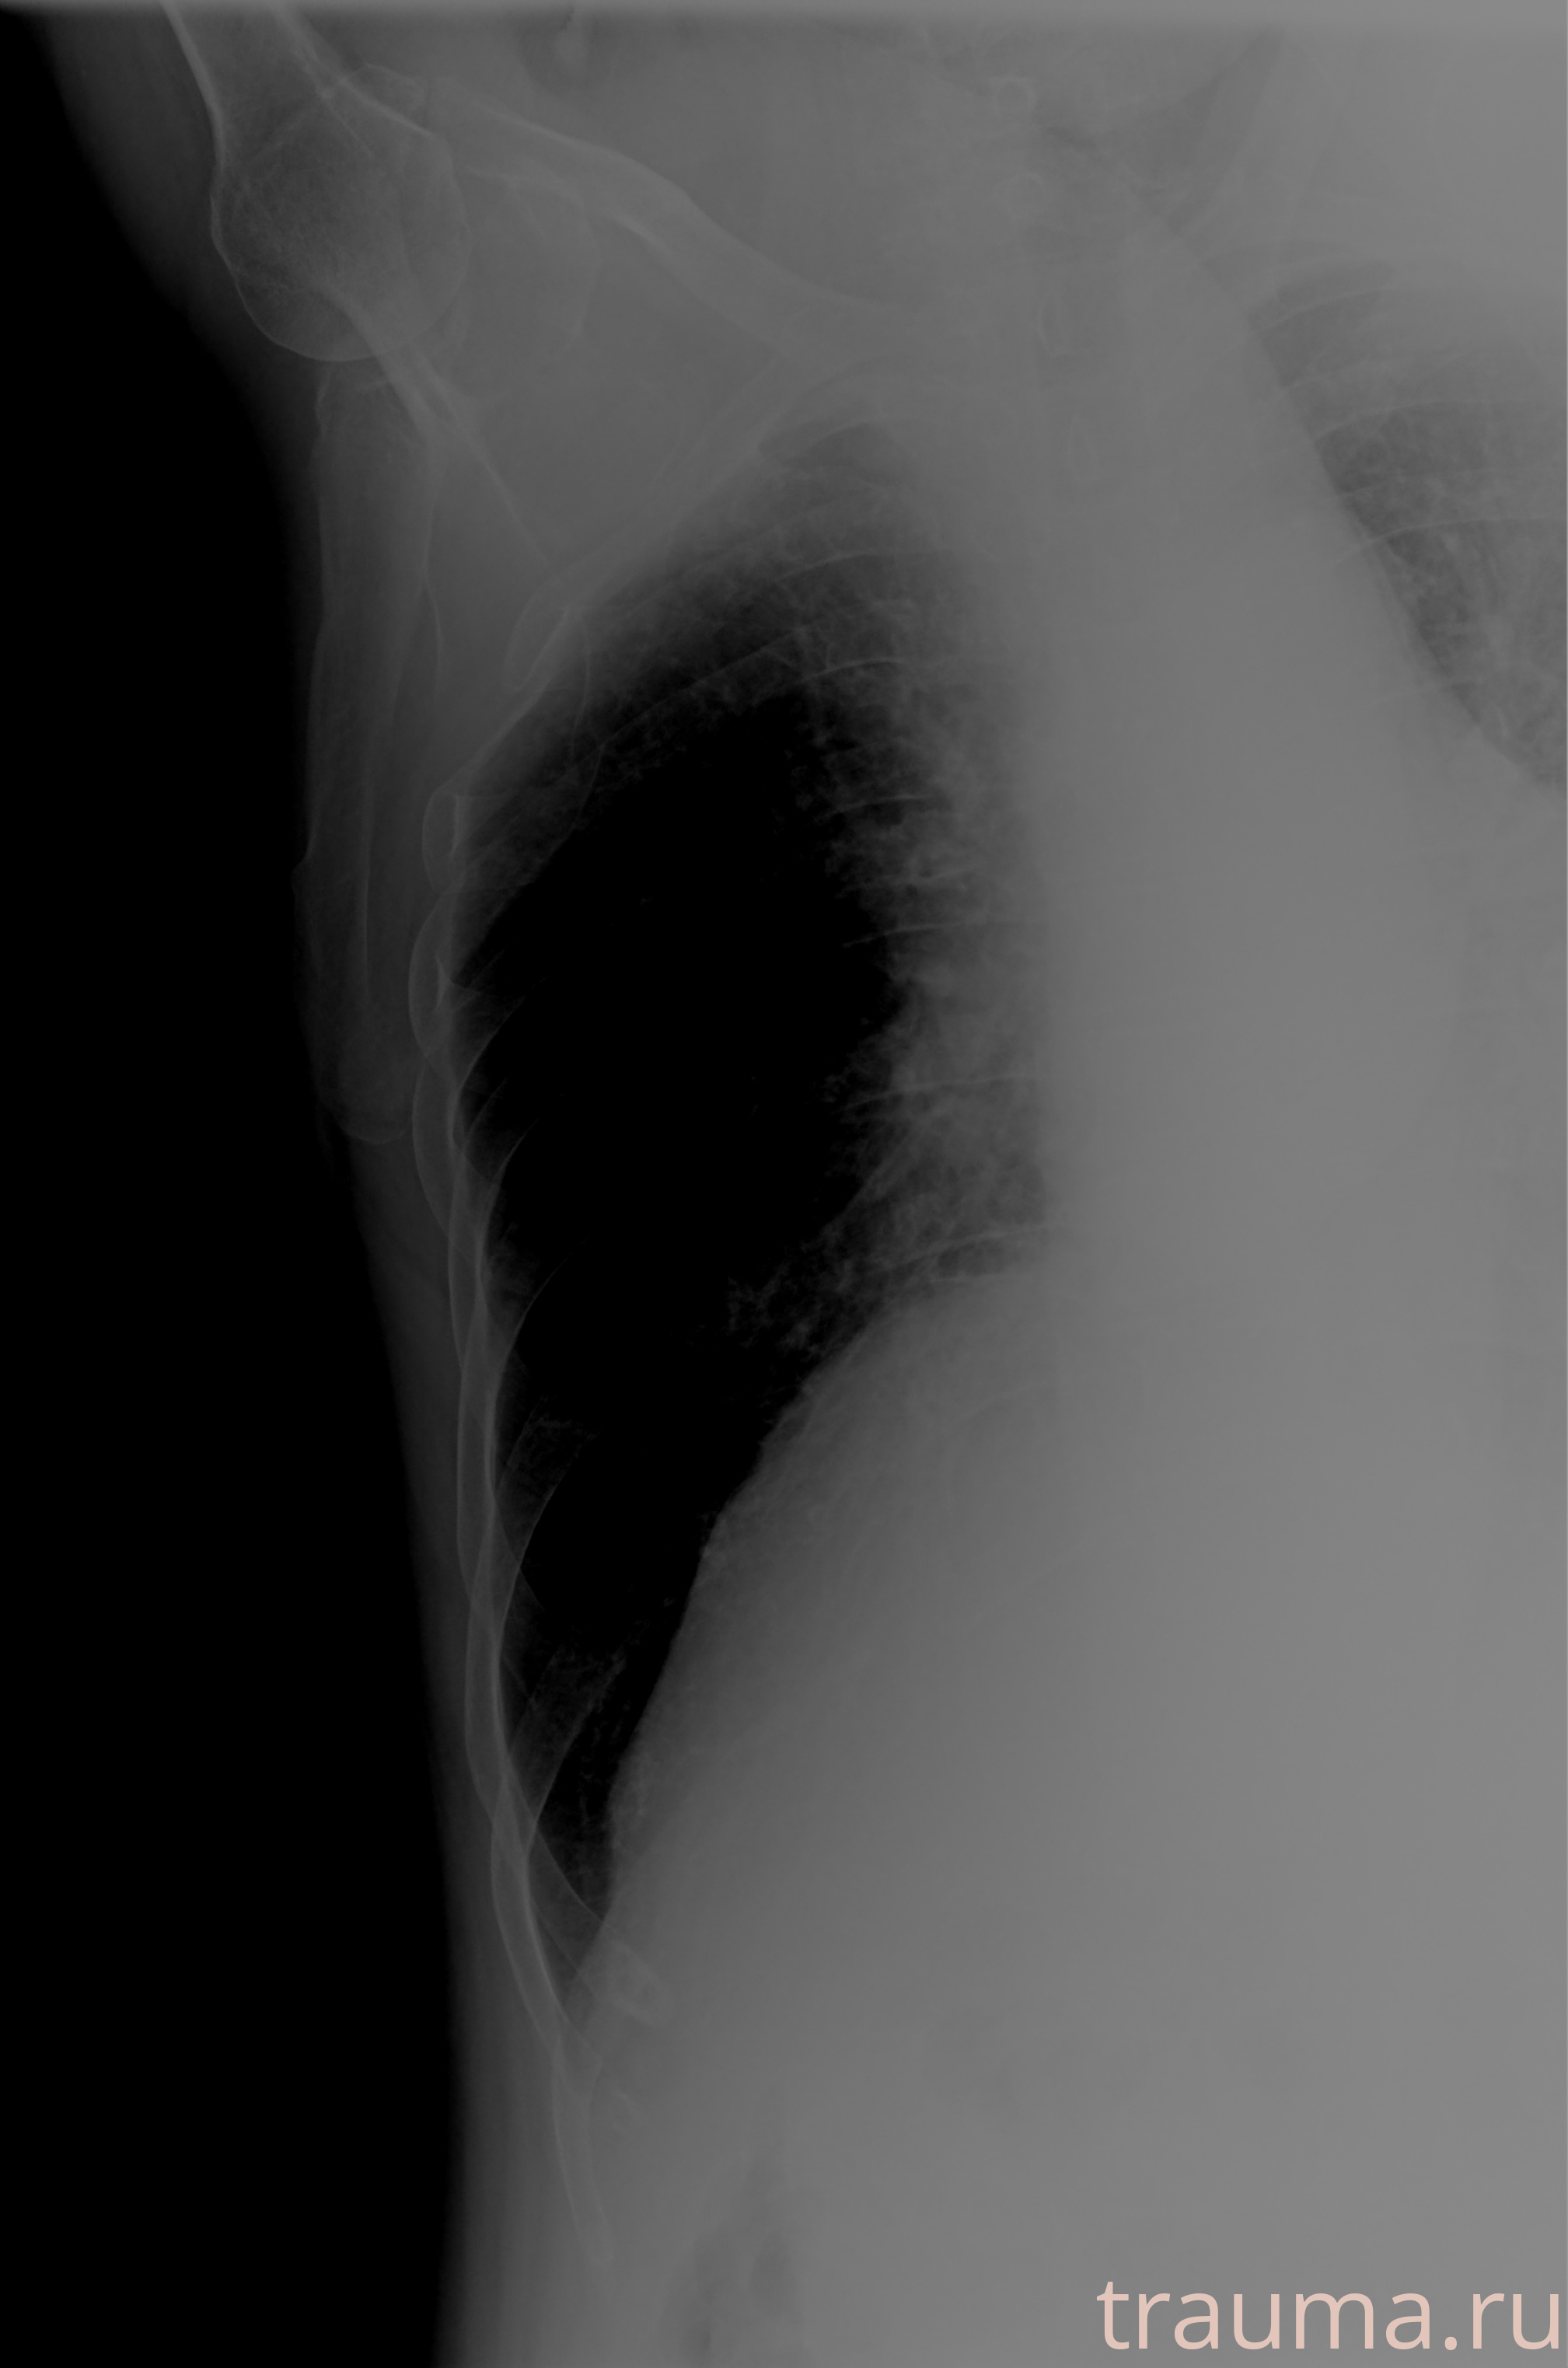

Рентгенограммы

Рентген на дому: по вашему адресу приезжает врач-рентгенолог, травматолог-ортопед с мобильным рентгеновским аппаратом, проводит диагностику травмы или заболевания, делает необходимые рентгенограммы, дает рекомендации по дальнейшему лечению. Получить качественные снимки в домашних условиях возможно благодаря уникальной методике, разработанной МосРентген Центром для института  Склифосовского